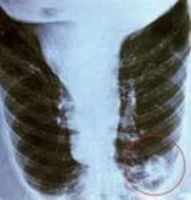

X線檢查:

1.CT肺炎可見瀰漫性間質性病變及斑片狀肺浸潤伴肺氣腫

2.CPN肺炎多為單側節段性浸潤,下葉及周邊多見,少數可有雙側病變http://www.huoguan.com。重症可伴發胸腔積液。肺部體徵和X線所見往往經過1個多月才消失。鸚鵡熱衣原體肺炎表現為由肺門向外放射的浸潤病灶,常侵及兩肺下葉,呈瀰漫性間質性肺炎或支氣管肺炎改變,偶見粟粒樣結節或實變灶,或有胸腔積液徵象。